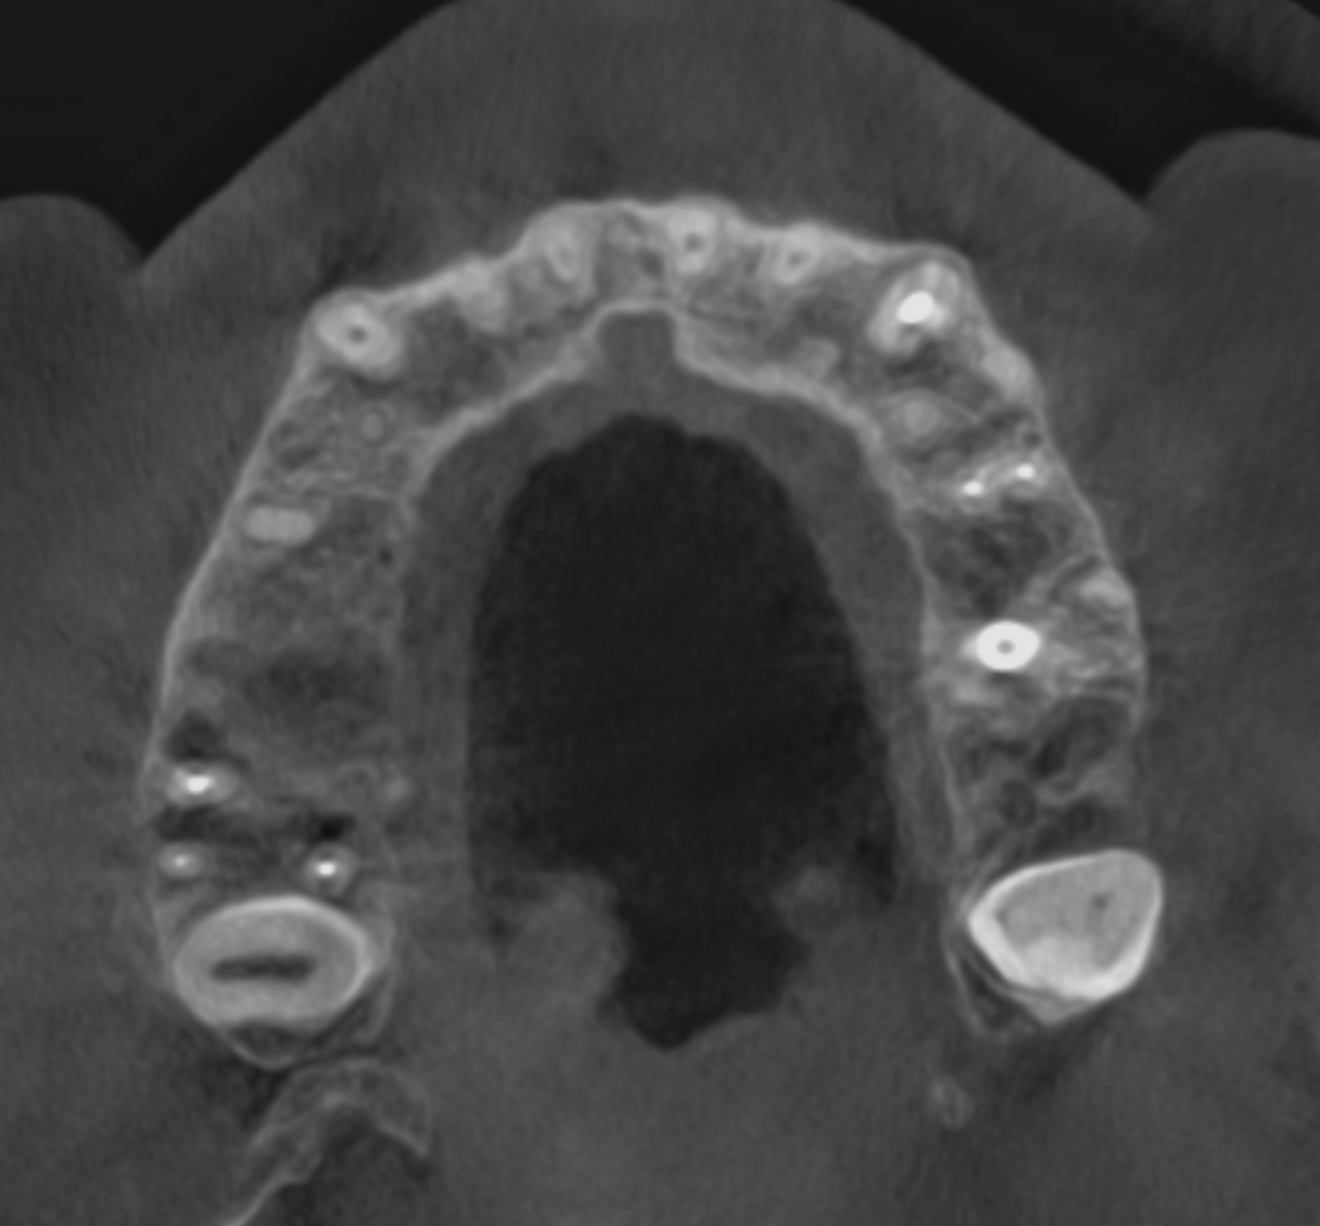

Figs. 10a & b: CBCT scan taken 12 weeks later showing complete healing, panoramic view (a) and cross-section of tooth #17 (b).

As a follow-up, we took a CBCT scan 12 weeks after the obturation, and it clearly showed that both the periapical tissue as well as the paranasal sinuses had recovered fully (Fig. 7). Newly formed cortical and cancellous bone was visible around the buccal and palatal roots (Figs. 8a & b) and extended in the caudal direction. Furthermore, all the paranasal sinuses were clear, and no epithelial widening was visible (Figs. 9a-f).

The bottom line is that it is really essential to locate the origin of our patients’ problem and evaluate its consequences to give proper treatment that facilitates complete regeneration of not only the periapical area but also the entire area of the paranasal sinuses (Figs. 10a & b). This can help the body and the immune system to achieve miraculous healing with a non-invasive treatment protocol.